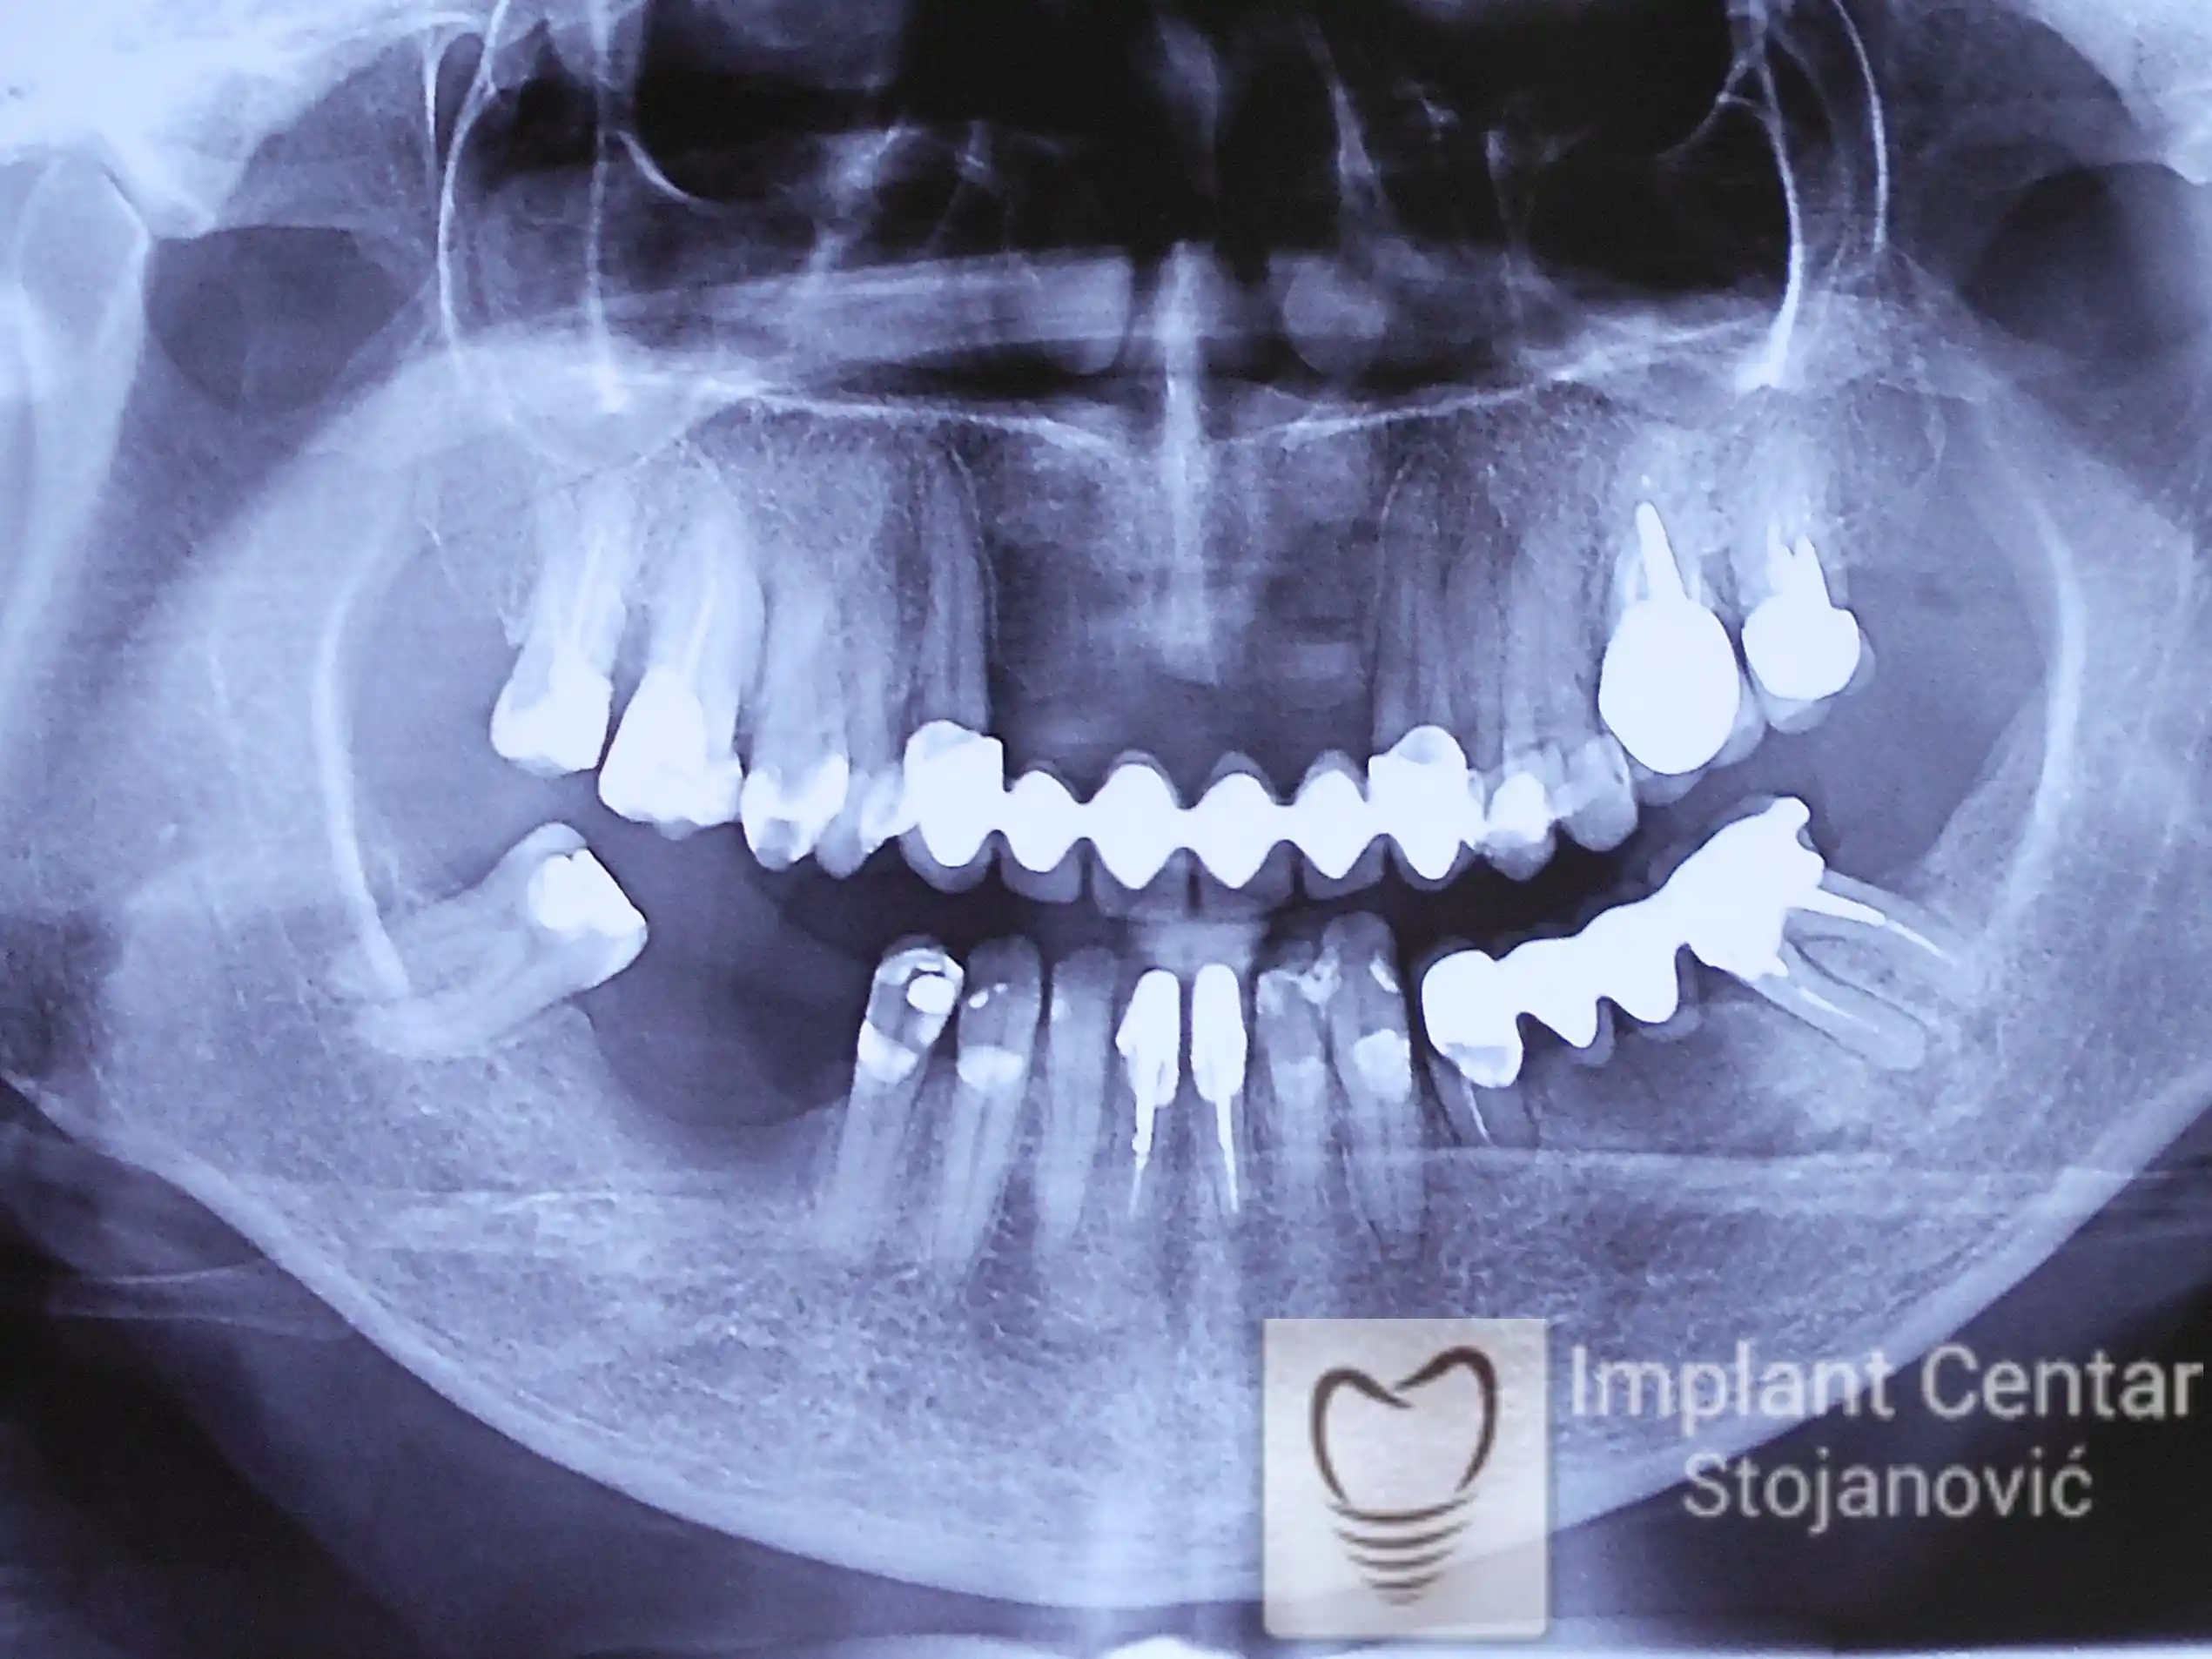

Pacijent sa rascepom usne, nepca i alveolarnog grebena uspešno je rehabilitovan fiksnim protetskim radom na implantatima. Pre dolaska u našu ordinaciju, pacijent je u gornjoj vilici nosio totalnu protezu preko preostalih zuba, dok je u donjoj vilici bio zbrinut parcijalnom mobilnom protezom. Tokom višegodišnje potrage za adekvatnim rešenjem, pacijent nije uspeo da pronađe zadovoljavajuću terapijsku opciju ni u zemlji ni u inostranstvu.

Nakon detaljnog kliničkog pregleda i analize radioloških snimaka, izrađen je sveobuhvatan plan terapije sa ciljem uklanjanja mobilnih proteza i postizanja maksimalne funkcionalne i estetske rehabilitacije. Zbog loše biološke vrednosti preostalih zuba, doneta je odluka o njihovom vađenju i ugradnji dentalnih implantata.

Poseban terapijski izazov predstavljalo je premošćavanje defekta nastalog usled rascepa, kao i ograničena količina raspoložive kosti u gornjoj vilici. Primenom većeg broja implantata i odgovarajućih procedura nadoknade kosti, postignuta je stabilna osnova za fiksni protetski rad.

Tokom perioda oseointegracije, pacijent je bio zbrinut fiksnim privremenim krunicama, čime je već pet dana nakon intervencije obezbeđena potpuna funkcionalna i estetska rehabilitacija. Nakon završetka perioda integracije implantata, izrađeni su definitivni cirkonijum-keramički mostovi na implantatima.